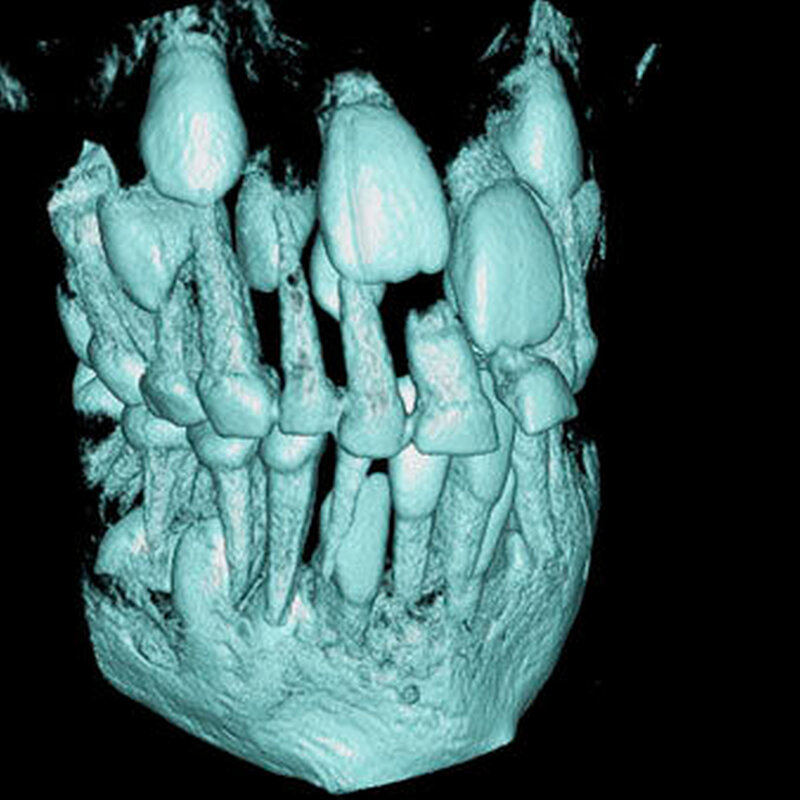

Überzählige Zähne können einzeln oder multipel auftreten [von Arx, 1990; Rajab Hamdan, 2002; Fernández Montenegro et al., 2006; Liu et al., 2007; Gündüz et al., 2008; Ferrés-Padró et al., 2009; Hyun et al., 2009]. Einzelne überzählige Zähne treten in 65,8 bis 80,5 Prozent, doppelte in 14,5 bis 27,7 Prozent und multiple in 0,6 bis 8 Prozent der Fälle auf [Rajab Hamdan, 2002; Fernández Montenegro et al., 2006; Liu et al., 2007; Ferrés-Padró et al., 2009; Hyun et al, 2009; Mossaz et al., 2014]. Einzelne oder doppelte überzählige Zähne finden sich typischerweise in der Oberkieferfront [Rajab Hamdan, 2002; Fernández Montenegroet al., 2006; Mossaz et al., 2014]. Multiple überzählige Zähne werden vor allem im Prämolarenbereich des Unterkiefers gefunden [Abbildung 4; YUSOF 1990, Ferrés-Padróet al., 2009; Wang Fan, 2011]. Multiple überzählige Zähne sind zudem oft mit anderen Erkrankungen oder Syndromen assoziiert, dazu gehören Lippen-Kiefer-Gaumenspalten, die cleidokraniale Dysplasie oder auch das Gardner-Syndrom. Bei Patienten mit einer Lippen-Kiefer-Gaumenspalte wird vermutet, dass sich die überzähligen Zähne aus der Fragmentierung der dentalen Lamina bei der Spaltbildung ergeben [Garvey et al., 1999; Wang Fan, 2011].

Überzählige Zähne werden nach ihrer Lage im Zahnbogen und auch aufgrund ihrer Morphologie eingeteilt. Basierend auf der Lage unterscheidet man bei überzähligen Zähnen zwischen Mesiodens (Oberkiefer median), zwischen den zentralen Inzisiven (Abbildungen 5 und 6), einem zusätzlichen Schneidezahn (zentral oder lateral), Eckzahn, Prämolar (Abbildung 7), Paramolar und Distomolar (Abbildungen 8). Mesiodentes werden am häufigsten dia- gnostiziert, wobei Prozentsätze zwischen 38,8 Prozent bis 86,3 Prozent der überzähligen Zähne in der Literatur zu finden sind [Salcido-García et al., 2004/38,8 Prozent, Fernández Montenegro et al., 2006 /46.9 Prozent; Mossaz et al., 2014/48.5 Prozent; Ferrés-Padró et al., 2009/53.2 Prozent; Schmuckli et al., 2010/75 Prozent; Rajab Hamdan 2002/83.2 Prozent; Liu et al., 2007/86.3 Prozent]. Überzählige Prämolaren und seitliche Schneidezähne sind die zweithäufigste Gruppe der überzähligen Zähne. Überzählige Eckzähne, Paramolaren und Distomolaren dagegen gelten als eher selten [Rajab Hamdan, 2002; Salcido- García et al., 2004; Liu et al., 2007; Ferrés-Padró et al., 2009; Schmuckli et al., 2010; Mossaz et al., 2014]. Einzig eine Spanische Gruppe [Fernández Montenegro et. al., 2006] berichtete, dass Paramolaren und Distomolaren insgesamt relativ häufig seien (18 Prozent, beziehungsweise 5,6 Prozent). Überzählige Zähne kommen im Ober- und Unterkiefer vor, wobei sich überzählige Schneidezähne in der Regel im Oberkiefer, überzählige Prämolaren sich dagegen eher im Unterkiefer befinden [Fernández Montenegro et al., 2006; Ferrés-Padró et al., 2009; Mossaz et al., 2014]. Überzählige Molaren wiederum treten normalerweise im Oberkiefer auf [Cassetta et al., 2014; Kaya et al., 2014].

Bei überzähligen Zähnen werden vier morphologische Typen unterschieden: konisch (Abbildung 9), tuberkulär (höckerförmig; Abbildung 10), überzählige Zähne mit identischer Zahnform (Abbildung 11) und Odontom (Abbildung 12) [GARVEY et al. 1999]. Der konische überzählige Zahn ist ein kleiner, zapfenförmiger Zahn und zudem der häufigste Fall im bleibenden Gebiss [Rajab Hamdan 2002, Liu et al. 2007, Gündüz et al., 2008; Ferrés-Padró et al., 2009; Hyun et al., 2009; Schmuckli et al., 2010; Mossaz et al., 2014]. Er kommt oft zwischen den oberen zentralen Schneidezähnen vor und entwickelt sich gleichzeitig zur Wurzelbildung der bleibenden Schneidezähne. Konische überzählige Zähne führen meist nicht zu einer Durchbruchstörung oder -behinderung der zentralen Schneidezähne. Tuberkuläre, überzählige Zähne sind größer als der konische Typ und besitzen einen zusätzlichen charakteristischen Höcker oder Tuberkel der Zahnkrone. Sie kommen oft gepaart vor und liegen in der Regel palatinal der oberen mittleren Schneidezähne. Im Gegensatz zu konischen überzähligen Zähnen brechen die meisten tuberkulären nicht in die Mundhöhle durch und es kommt nicht selten zur Durchbruchstörung oder -behinderung der zentralen Schneidezähne [Mason et al., 2000; Minguez-Martinez et al., 2012]. Überzählige Zähne mit identischer Zahnform sind Zähne, welche vom eigentlichen Zahn in der Lage (also in der Zahnreihe gelegen) und Form nicht zu unterscheiden sind.